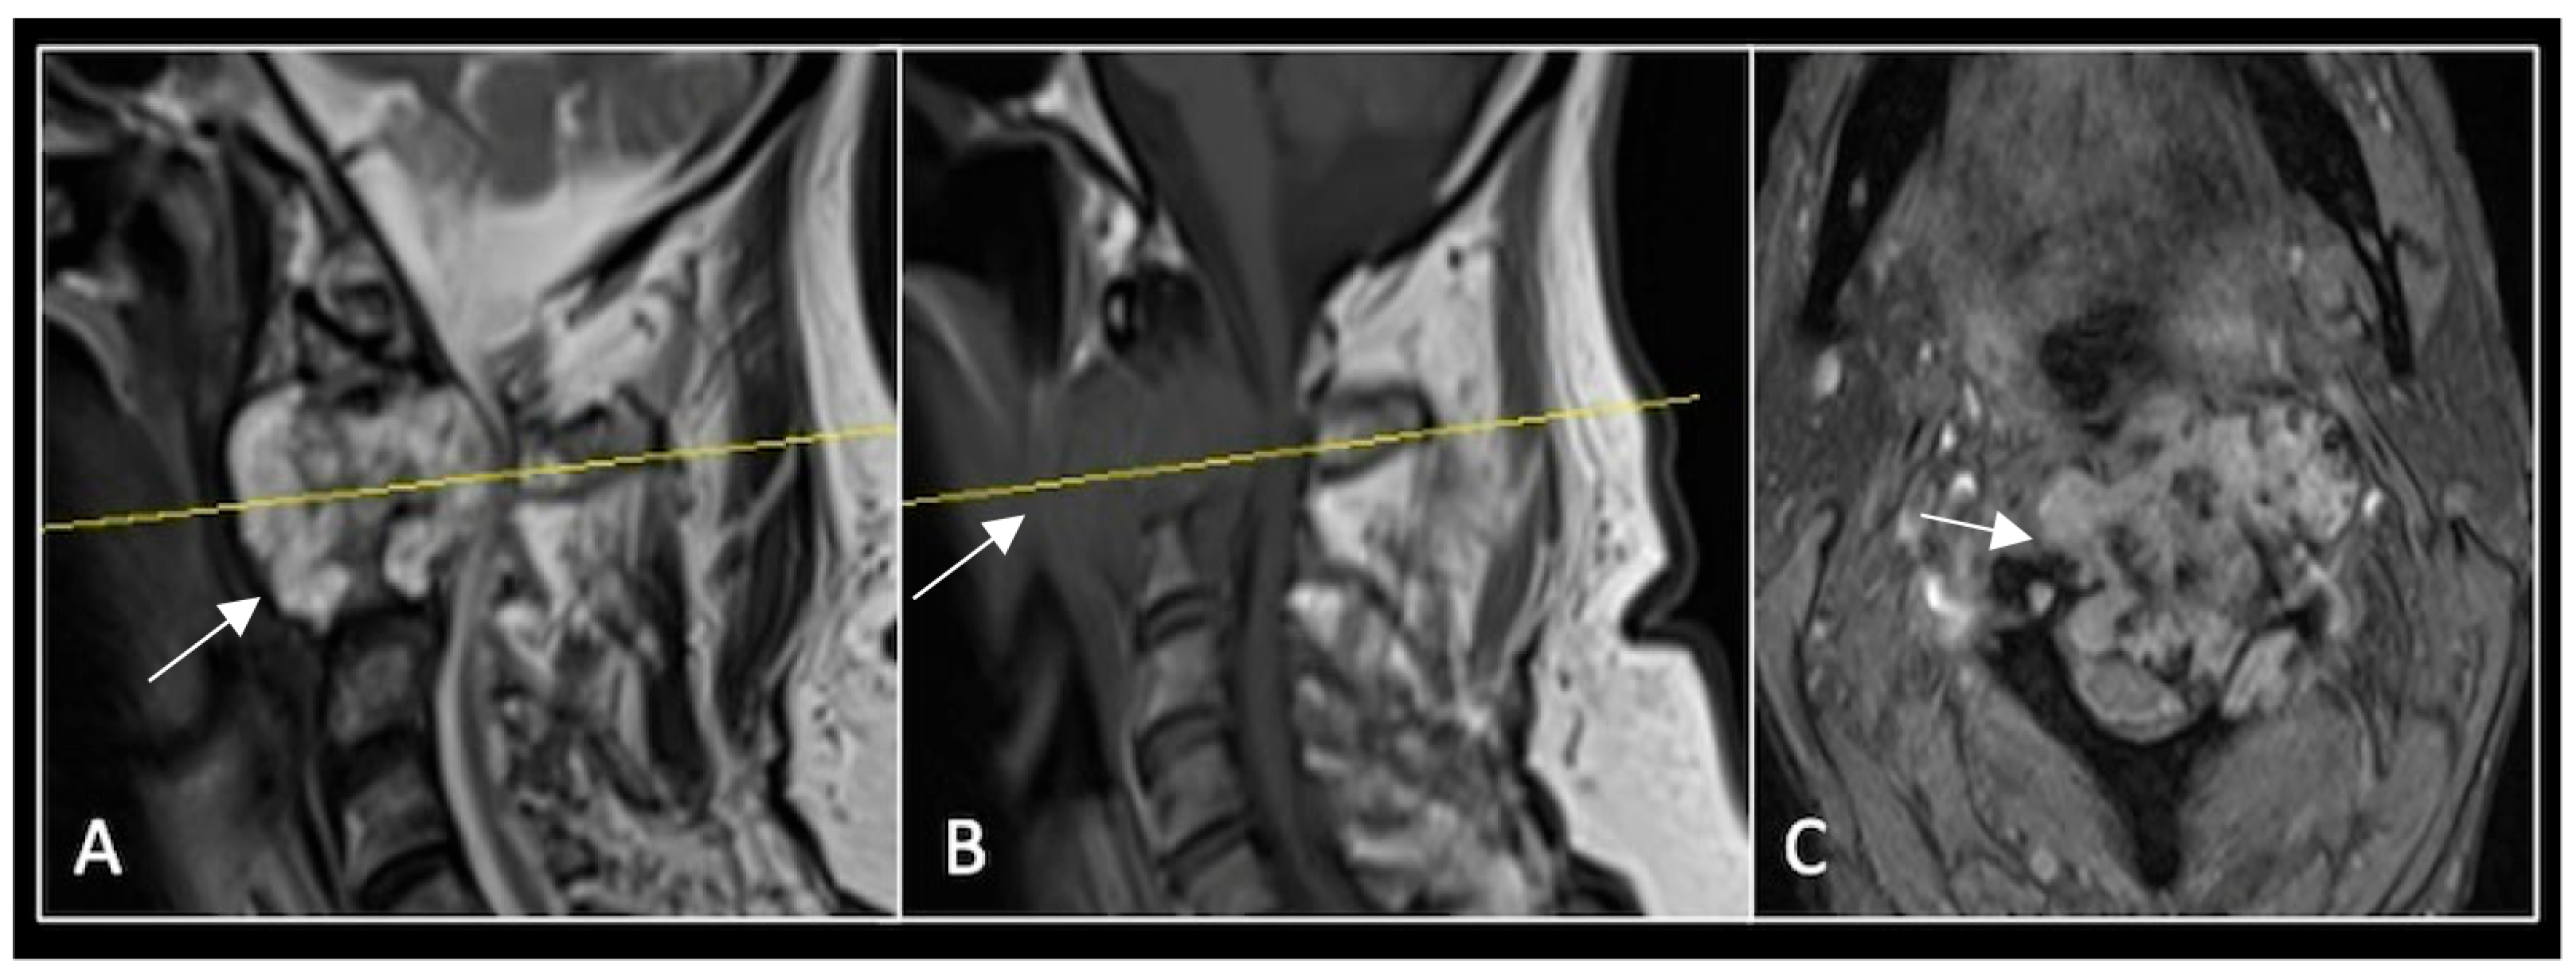

This 68-year-old male was referred to our institution with a 4 cm cervical mass localised to C2/3 following investigations for left-ear congestion and altered hearing (Figure 7). A CT-guided biopsy confirmed a conventional chordoma. The patient underwent separation surgery with adjuvant proton beam therapy. There was no evidence of disease progression on 3-monthly surveillance imaging (Figure 8). Approximately 12 months following separation surgery, the patient presented with acute onset neck pain. A C2 odontoid peg fracture was diagnosed requiring a posterior occipitocervical stabilisation procedure (Figure 9). Pre-stabilisation MRI imaging confirmed no tumour progression (Figure 10).

Figure 7.

The MRI demonstrates a left-sided lobular mass (arrow) with invasion of the C2/3 vertebral body and epidural extension, but no cord compression. The yellow line on the axial image indicates the axial slice level. (A) T2W sagittal; (B) T1W sagittal; (C) T2W axial.

Figure 8.

MRI demonstrating a left-sided posterior approach to the cervical spine with significant reduction in residual gross tumour volume (arrow) and circumferential decompression of the spinal cord. The yellow line on the sagittal images denotes the level corresponding to the axial section. (A) T2-weighted sagittal; (B) T1-weighted sagittal; (C) T2-weighted axial.